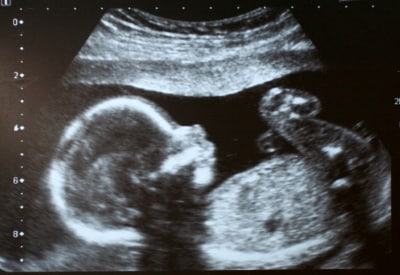

Ultrasound

Figure 8: Ultrasound 2D image using 85 db pulses.

Ultrasound is effectively a high-frequency sonar system, measuring the minute echoes of sound waves as they pass through the body. Ultrasound images (see Figure 8) resemble x-rays except that they are displayed in real-time.